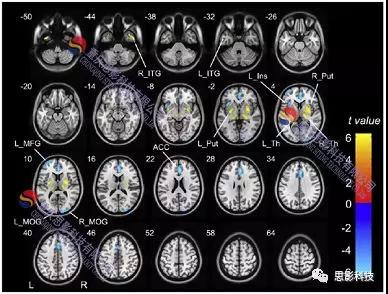

2.CBF統(tǒng)計計算:

1)構建單被試廣義線性模型

2)組水平分析

統(tǒng)計比較(t檢驗、方差分析、回歸分析等)

提取特定腦區(qū)信號與行為(臨床)數(shù)據(jù)進行進一步統(tǒng)計分析(如相關)。